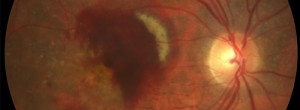

DMAE atrofica

· 19/03/2014

IN-EyE: Ensayo clínico en pacientes naive con neovascularización coroidea secundaria a la DMAE